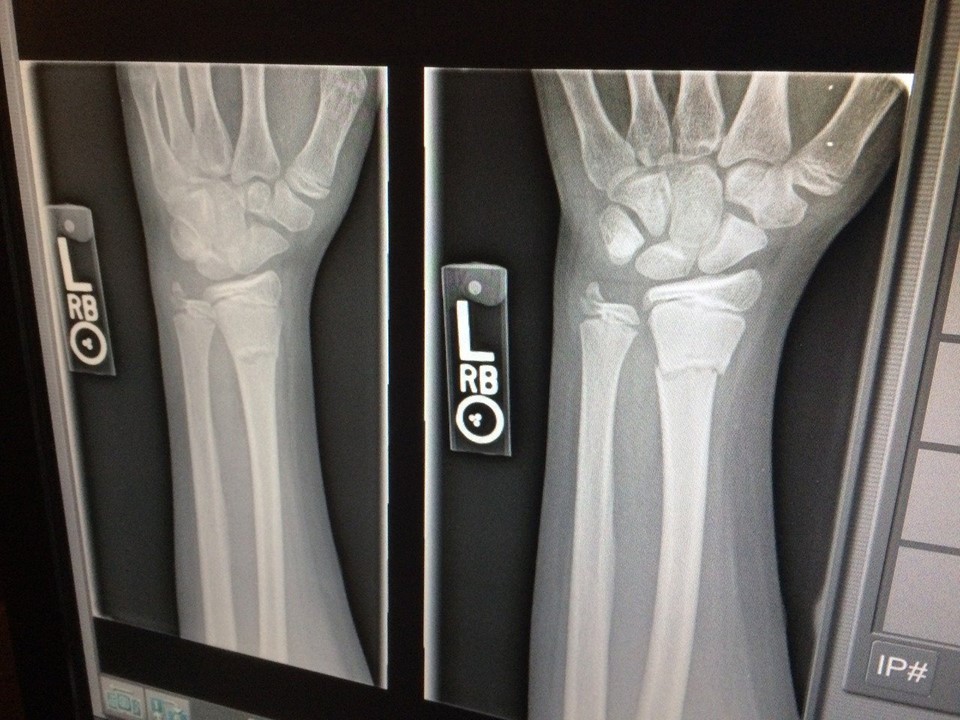

Gotovo svaka četvrta žena starija od šezdeset godina boluje od osteoporoze. Žene s prijevremenom ili kirurškom menopauzom, kod kojih su jajnici odstranjeni prije 45-te godine života su podložnije obolijevanju. Rizik osteoporoze povisuju nježna tjelesna građa i nizak rast, neuravnotežen menstrualni ciklus tijekom reproduktivne faze, anoreksija, fluoriranje vode, alkoholizam i pušenje. Osteoporozu potiču ne samo nedostatak tjelovježbe, pušenje i uživanje kofeina, već i prehrana temeljena na velikoj količini rafiniranih ugljikohidrata, manjak kalcija, magnezija, bora, vitamina D3, kao i depresija. Prvi znakovi bolesti su značajan gubitak u tjelesnoj visini i pogrbljeno držanje, bol u leđima, sklonost prijelomima (i to u području kuka, ručnog zgloba i kralješnice). Simptomi se javljaju tek kod pojave prijeloma, pa je osteoporoza najvećim dijelom asimptomatska bolest.

Klinički pregled omogućuje usmjeravanje dijagnostičkih postupaka i ukazuje na prisustvo drugih bolesti s nepovoljnim učinkom na koštani sustav. Osim kliničkog pregleda u dijagnostici se koriste laboratorijski parametri (krvne pretrage, kalcij, fosfor, AP, kreatinin, gamaGT, hormonske pretrage: TSH, FSH, LH, E2, PTH, vit. D3 i biokemijski markeri koštanog metabolizma), rendgensko slikanje, kao i denzitometrija. Najvažniji parametar kod denzitometrije je T-Score: broj standardnih odstupanja nalaza koštane gustoće od maksimalne koštane mase (PBM - Peak Bone Mass). Na osnovu T-Scora razlikuju se četiri stadija osteoporoze:

- Osteopenija - smanjena koštana gustoća: T Score= -1.0 do -2.5, nema prijeloma,

- Osteoporoza: T-Score= -2.5, nema prijeloma,

- Manifestna osteoporoza: snižena gustoća kostiju, 1 - 3 prijeloma kralježaka bez adekvatne traume,

- Uznapredovala osteoporoza: snižena gustoća kostiju, mnogobrojni prijelomi kralježaka, ali i ekstraspinalni prijelomi.

Prijelomi kostiju, osobito u starijoj životnoj dobi ostavljaju značajne posljedice. Velikom broju pacijenata je neophodno dugotrajno stacionarno ili ambulantno liječenje. Najčešći razlog bolova u predjelu leđa i križa su osteoporotičke deformacije kralježnice. Nije za zanemariti niti smrtni ishod kod oko 20% pacijentica s prijelomom bedrene kosti.